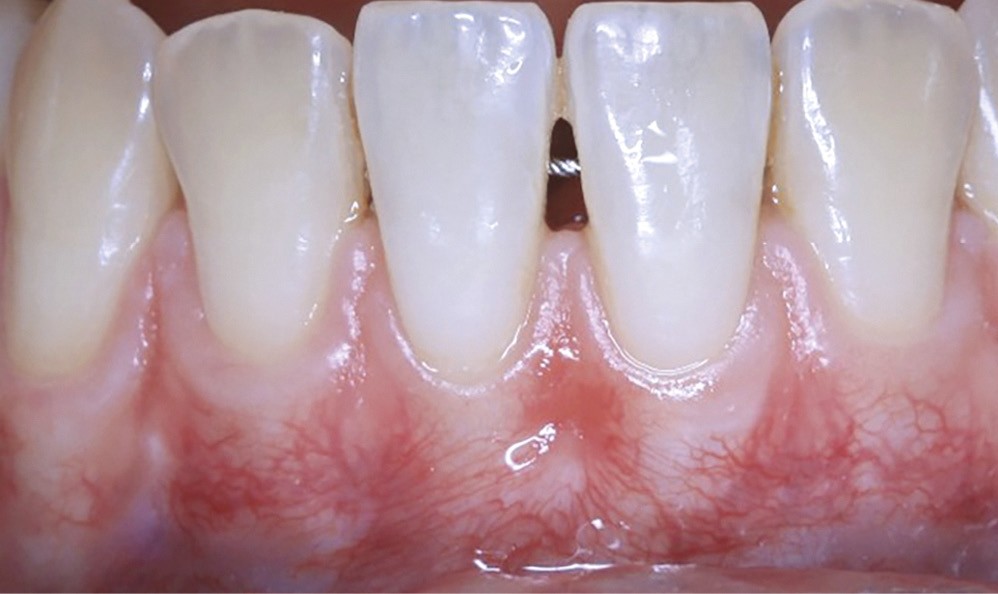

Les greffes de tissu conjonctif consistent en l’insertion d’un greffon de tissu conjonctif prélevé dans la cavité buccale, sous un lambeau déplacé (avec ou sans décharges), une enveloppe ou un tunnel. C’est la technique de choix pour le recouvrement radiculaire [13], que ce soit pour des récessions unitaires ou multiples, mais elle est aussi indiquée dans l’augmentation en épaisseur des parodontes fins avant traitements prothétiques, orthodontiques ou implantaires.

De nombreuses techniques de lambeaux déplacés latéralement, lambeaux déplacés coronairement (fig. 4), enveloppes ou tunnels (fig. 5) ont fait l’objet de publications et présentent des résultats quasi identiques en termes de recouvrement. Leurs points communs sont un recouvrement complet du greffon, une dissection en épaisseur partielle suffisante pour assurer un positionnement du lambeau sans tension et l’absence (quand cela est possible) d’incision de décharge. Le choix d’une ou l’autre technique dépend surtout de l’expérience du praticien et de la quantité de tissu disponible apicalement ou latéralement.